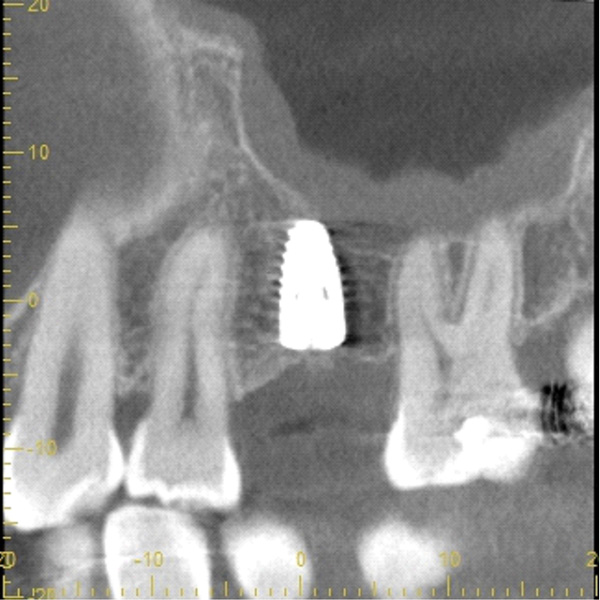

| 年代・性別 | 50代 男性 |

|---|---|

| 主訴 | 右下の歯がないのでインプラントをして欲しい |

| 治療期間 | 約6ヶ月 |

| 費用 | 600,000円 |

| 治療内容 | インプラント、骨造成、結合組織移植、セラミック修復 |

| 治療に伴うリスク | インプラント周囲炎 セラミックの破折、脱離 |